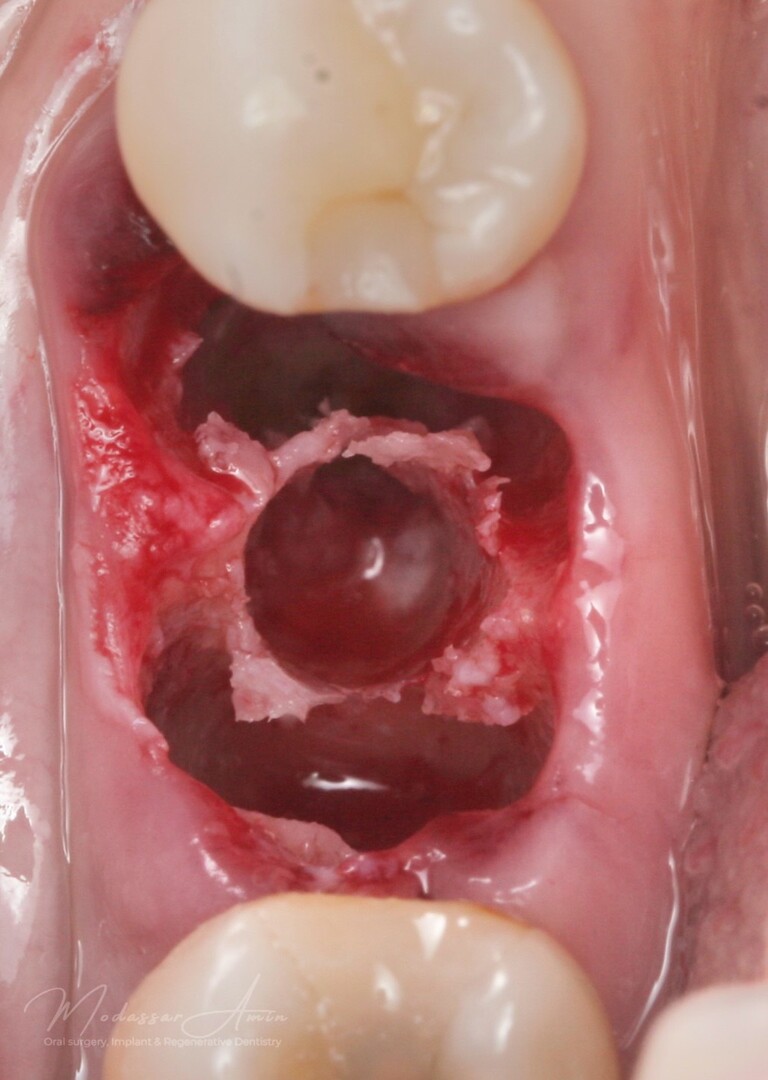

PATIENTFALL

"Pasienten presenterte med tann 46 som ikke kunne bevares grunnet en dyptgående infraksjon inn i furkasjonen. Forholdene lå til rette for en immediate implantatbehandling. Ved hjelp av Versah osseodensifikasjonsbor ble det interradikulære beinet ekspandert på en skånsom og forutsigbar måte, noe som ga høy primærstabilitet (>40 Ncm) til tross for en lokal bendefekt apikalt mesialt etter kronisk apikal periodontitt. Den gode stabiliteten muliggjorde bruk av SSA (Sealing Socket Abutment) for forsegling. På grunn av tynn bløtvevsfenotype bukkalt ble behandlingen supplert med bindevevstransplantat (CTG)"

Expanderat septum

God primär stabilitet på 40+ ncm

SSA (Sealing Socket Abutment) + CTG (bindvävstransplantat)